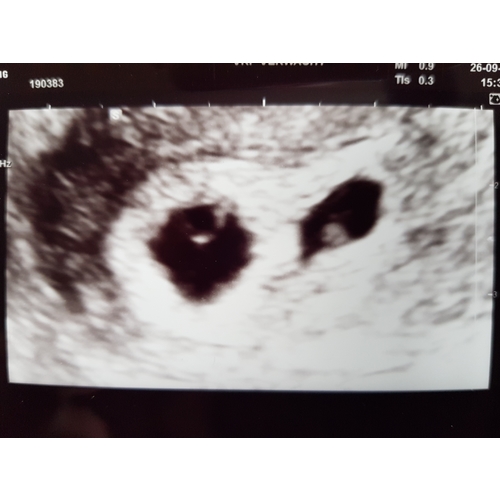

Dit is mijn echo van gisteren 5+5. Ook 2 vruchtzakjes en bij beide een hart ...

Ik ging naar de verloskundige met hele erge buikkrampen. Kreeg voor de zekerheid een echo omdat het me niet lekker zat en we volgende week op vakangie gaan naar het buitenland. Tijdens de echo zag ze eerst 3 holtes.. Toen schrok vooral mijn man heel erg.. toen ze daarna zei, het zijn er 2.. viel het voor ons dus alweer mee! Het is onze eerste zwangerschap, dus allemaal super spannend en nieuw. Verloskundige dacht dat ik ongeveer 5 +5 zwanger ben en dat het daarom nog even afwachten is hoe het zich verder ontwikkeld omdat dit wel een hele vroege echo was. Wel beide hartjes zien kloppen.. durf er nog niet van uit te gaan dat het allemaal goed gaat, omdat ze zelf ook eerst de volgende echo wilde afwachten. Vind het dus vooral spannend of het over anderhalve week nog steeds allemaal goed is. Hoe was het bij jou?